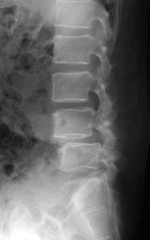

腰椎の「ずれ」についてはX線(レントゲン)検査で診断します。

腰椎を前後に曲げた状態での撮影で、より明確に診断がつきます。

第4腰椎が前方(図の左側)へ移動している